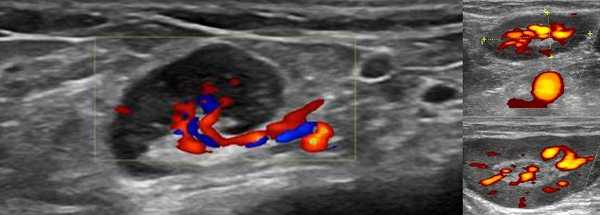

На сегодняшний день основное место в определении состояния сонных и позвоночных артерий занимает ультразвуковое цветовое дуплексное сканирование (ультразвуковая допплерография или УЗДГ).

Исследование объединяет построение 2D-изображений и анализ целевых сосудов. Принцип регистрации данных УЗ-аппаратом заключается в разнице получения сигналов от статичных и движущихся объектов. Первые видны на мониторе в серой шкале, вторые - как участки красного и синего цветов, показывающие направление кровотока. Скорость последнего позволяет судить о выраженности окклюзии и количестве зон со сниженной перфузией.